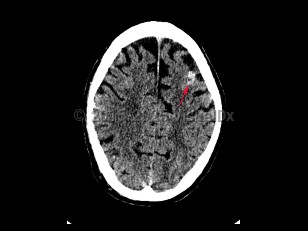

Subarachnoid hemorrhage (SAH) is bleeding directly into the cerebrospinal fluid (CSF) within the subarachnoid space that surrounds the brain. It usually presents as a severe sudden-onset headache, often described as the worst headache of the patient's life, with radiation of pain down the neck and back. Onset of headache may be accompanied by a brief loss of consciousness, nausea, vomiting, and meningismus. SAH occurs in about 10 per 100 000 people per year. Incidence increases with age and peaks in the sixth decade of life. Risk factors include female sex, smoking, alcohol use, drug abuse, hypertension, oral contraceptive use, known cerebral vascular malformation, collagen vascular disease, and family history of SAH. In the United States, African Americans are at higher risk.

Cerebral aneurysms > 5-7 mm are most likely to rupture. Approximately 1%-3% of patients visiting the emergency department for a headache are subsequently found to have a SAH. Trauma is the most common cause of SAH; however, nontraumatic SAH is found to result from a ruptured saccular aneurysm in 80% of cases. Patients with SAH require close monitoring and often require intensive care unit admission.

Approximately 10%-15% of patients die before reaching medical care. Even with appropriate care, the mortality rate from SAH is approximately 25%-50%. About one-half of patients who survive have significant morbidity.